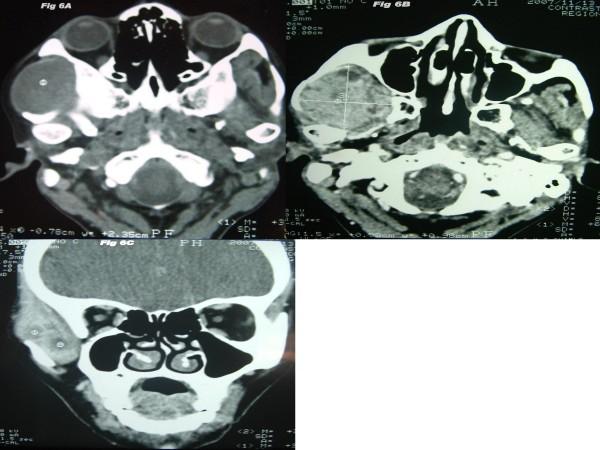

We present a case of a 41-year-old female that presented with swelling in the right preauricular region that had persisted for the past two years. The patient was diagnosed as having a small lymphocytic NHL. She initially underwent chemo-radiation but reported relapse. The tumor was excised and again the patient underwent chemotherapy. The patient remained symptomatic and developed a second primary squamous cell carcinoma in the right retromolar trigone.

我们报告一例41岁女性患者,其右耳前区肿胀持续两年。该患者被诊断为小淋巴细胞性NHL。她最初接受了放化疗,但出现复发。肿瘤被切除,患者再次接受化疗。患者仍有症状,并在右磨牙后三角区发生了第二原发性鳞状细胞癌。